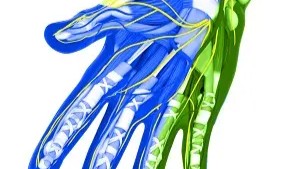

Birth brachial plexus palsy: a race against time. S Patra, JKN Kurup, AM Acharya, AK Bhat. BMJ case reports 2016, bcr2016215996.

pubmed.ncbi.nlm.nih.gov/27402656